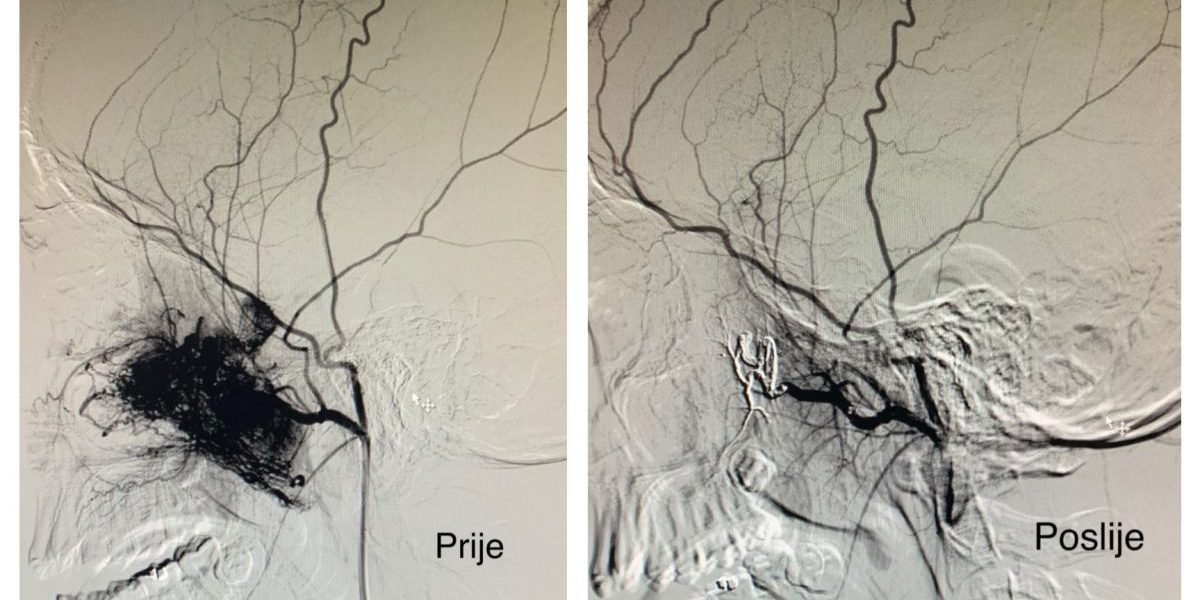

According to one of surgeons Hasan Altumbabić, MD, MSci., the first step in the treatment is transchateter embolization to shut down the blood supply to a tumor, which is then surgically removed. In case when the tumor has already spread to the brain cavity and cannot be surgically removed, radiotherapy is being applied. ” Our patient is a 14- year- old boy who had a car accident 6 months ago. He has not been breathing through his right nostril for 3 months and has frequent nasal bleeding. After additional neuroradiological assessment and CT angiography, juvenile angiofibroma that destroyed the inner wall of the eye cavity and partly the base of the brain with the endocranial propagation was suspected, and surgical treatment was indicated. ” said Dr. Altumbabić and explained that he surgery was done in two phases. In the first phase the embolization of blood vessels was done uneventful at the Clinic for Neurosurgery. In the second phase the tumor was surgically removed, and the resulting defect was reconstructed at the ENT Clinic. Dr. Altumbabić also said that the early postoperative recovery of the patient is going well.

The procedure of the embolization of blood vessels performed Ass. Prof. Mirza Moranjić and Dr. Adnan Čičkušić. The surgical team of the ENT Clinic consisted Dr. Hasan Altumbabić, Dr. Emir Šehanović, Dr Zlatka Džinić- Jusufović, dr. Samir Hodžić anesthesiologist, Indira Okanović anesthetician, and Alija Suljagić scrub technician.